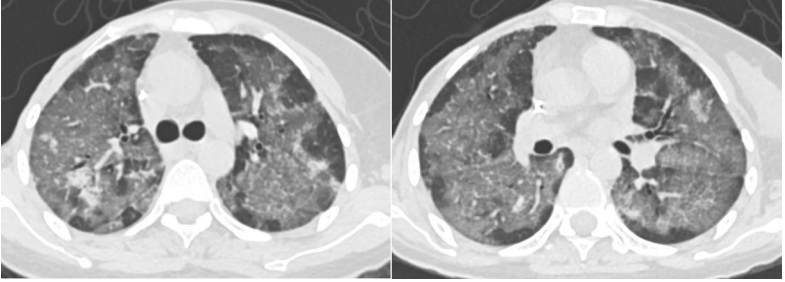

患者,女,50岁;活动后喘息20天,加重伴发热3天,2021年11月19日转入我院。入院胸部CT显示:双肺实变,磨玻璃影(图1)。11月24日复查胸部CT可见病变进展迅速(图2)。予患者气管插管机械通气、俯卧位等,呼吸衰竭未见改善。遂于11月25日启动VV-ECMO(转速2860 rpm,流量4.5 L/min,氧浓度100%)。追问病史:患者入院前1月有活动后气促症状,自觉全身不适,近2年有眼干、口干不适。进一步检查发现,ANA反应阳性(+),ANA核型为胞浆颗粒型(异常);抗SSA/Ro抗体阳性(++)、抗Ro-52抗体阳性(+++)。诊断:急性间质性肺炎(AIP);Ⅰ型呼吸衰竭;混合性结缔组织病。治疗:VV-ECMO+呼吸机辅助通气+俯卧位通气、激素(甲强龙80 mg×7天,60 mg×3天,40 mg qd)、免疫抑制剂(环磷酰胺400 mg qd×3天)、抗感染(哌拉西林他唑巴坦4.5 g q12h+莫西沙星0.4 g qd+氟康唑氯化钠注射液20 mg qd)、抗凝等。在随后的一段时间内,患者影像学改善不明显(图3)。直至12月20日,复查胸部CT可见患者肺部病变较前明显吸收(图4)。2021年12月31日VV-ECMO撤机后,继续气切呼吸机辅助通气,甲强龙40 mg qd抗炎治疗,继续抗感染治疗,2022年1月7日脱机,1月21日气管封管,1月26日出院。后续治疗:强的松25 mg qd,环磷酰胺600 mg q2w×4次,序贯吗替麦考酚酯0.5 g bid。重症间质性肺疾病(ILD)在诊断方面需要考虑以下问题:是ILD吗?是哪种ILD?严重程度如何?在治疗方面,除了生命支持(呼吸支持重点)和病因治疗,并发症的处理也至关重要。重症ILD的诊断包括两方面,一方面是通过影像学、病史+临床表现、BALF-NGS、实验室检查、肺活检等对ILD进行诊断;另一方面涉及重症,患者多面临呼吸衰竭甚至多器官衰竭,因此时间更加紧迫。在ICU内最常见的重症ILD包括:特发性肺纤维化急性加重(AE-IPF)、自身免疫相关性ILD、肿瘤治疗相关性ILD、隐源性机化性肺炎(COP)、AIP、过敏性肺炎(HP)、急性嗜酸性粒细胞性肺炎(AEP)、药物相关ILD等。在影像学方面,最易导致重症的类型有弥漫性磨玻璃影和实变影。最常见的鉴别诊断就是重症肺部感染。表现为弥漫性磨玻璃影或实变影的ILD较为多见,例如:HP、嗜酸性粒细胞性肺炎(EP)、结缔组织病相关间质性肺病(CTD-ILD)、非特异性间质性肺炎(NSIP)、脱屑性间质性肺炎(DIP)、淋巴细胞性间质性肺炎(LIP)、机化性肺炎(OP)、AE-IPF、肺泡蛋白沉积症(PAP)、肺泡微结石症、结节病、弥漫性肺泡出血综合征、肺水肿等。而很多感染性疾病影像学也可表现为磨玻璃影,例如:卡氏肺孢子菌肺炎(PCP)、病毒性肺炎、巨细胞病毒性肺炎、支原体肺炎。尽管如此,ILD也有部分影像学具有特征性,可以被识别。图5左表现为肺陷闭,也称为“猪头肉冻征”,这是典型的亚急性HP的影像学特征。图5右表现为弥漫性磨玻璃影,但以肺门向外扩展,外面有肺大泡,这是典型的PCP表现。临床上多见自身免疫性疾病导致的ILD,此类疾病也具有共同的特征,例如双肺弥漫,病理方面以NSIP或OP为主要特征。但也有部分患者可以出现弥漫性肺泡损伤(DAD)特征。如图6所示,左图为ANCA相关性血管炎,右图为MDA5相关性间质性肺病。因此,一定要警惕容易发生这种病理改变的自身免疫性疾病。

图6 ANCA相关性血管炎和MDA5相关性间质性肺病胸部CT表现病史和临床表现是临床医生特别是内科医生重要的诊断思维基础。重症ILD通常急性或亚急性起病,急性起病的ILD包括COP、AIP、AEP、HP;亚急性起病包括COP、药物相关性ILD、CTD-ILD、HP。急性、亚急性(可有发热)易误诊为肺炎。但也有一些重要线索可以帮助我们进行鉴别:季节性、聚集性发病多为感染;有免疫缺陷病史的患者多发生机会性感染;具有结缔组织病特征的患者要注意CTD-ILD;有肿瘤治疗史的患者注意考虑药物相关性ILD。当然,ILD也可以合并感染。病例:男性,28岁,高热,呼吸困难1周;1年前诊断肾病综合征,一直服用激素。T 39℃,安静状态,高流量氧疗(流速40 L/min,氧浓度70%),SaO2 93%。影像学表现为弥漫性磨玻璃影(图7)。首先考虑机会性感染—PCP。肿瘤治疗史是识别ILD的重要线索,许多肿瘤治疗新药可能会损伤肺部靶器官,例如免疫检查点抑制剂导致的间质性肺炎——免疫检查点抑制剂相关性肺炎(CIP),尽管其发生率不高,但由于此类治疗的基数较大,在临床上还是能经常见到CIP患者。所以需要了解患者免疫检查点抑制剂用药史以及影像学特征【新出现的肺部阴影(如磨玻璃影、斑片实变影、小叶间隔增厚、网格影、牵拉性支气管扩张及纤维条索影等)】,同时除外肺部感染、肿瘤进展、其他肺间质性疾病、肺血管炎、肺栓塞及肺水肿等。病例:患者, 女性, 32岁, 乳腺癌术后放化疗3年半, 靶向治疗4个月, 呼吸困难进行性加重1个月。影像学表现为磨玻璃影(图8), 氧合指数100 mmHg。诊断为药物相关性间质性肺炎。通常结缔组织病的相关体征,在呼吸系统无法识别,但一些肺外体征要引起重视,例如:眼周皮疹、披肩样皮疹、前胸V形皮疹、Gottron征、Gottron征、技工手。上述体征结合影像学表现就要考虑是否为ILD。二代测序(NGS)能够对常见和罕见的病原体进行检测,对新发病原体进行鉴定,也能鉴定常规方法难以检测的病原体,还能检测混合感染,进行菌株分型和耐药分析,在区分感染和定植方面有一定帮助。需要注意的是,对于支气管肺泡灌洗液(BALF)NGS结果,如果有强有力的证据认为不是感染,或者认为其检测出的是无意义的感染,结合患者肺部影像学为弥漫性间质改变,则要考虑非感染性疾病的诊断。病例:女性,75岁,反复咳喘3年,加重伴发热3天。曾诊断为特发性间质性肺炎,口服激素治疗1年。胸部CT可见磨玻璃影(图9)。BALF肺孢子菌核酸检测阳性,BALF-NGS回报肺孢子菌。后予激素和抗真菌治疗,患者最终好转出院。实验室检查应该作为ILD患者的常规筛查,CTD-ILD、IPAF筛查特异性抗体,结节病患者筛查ACE,系统性血管炎患者筛查ANCA。病例:女性,52岁,咳嗽15天,伴发热13天,抗Jo-1抗体阳性(+),CK、LDH增高;诊断为抗JO-1抗体综合征。患者胸部CT如图10所示。另外一例患者48岁, 全身起皮疹、关节疼痛伴发热2个月。抗黑色素瘤分化相关蛋白5(MDA5)抗体阳性; 诊断为肌病性皮肌炎-急性/亚急性间质性肺炎。患者胸部CT如图11所示。呼吸介入技术的发展为临床诊断和破解病因带来了极大的帮助,包括经支气管镜肺活检术(TBLB)、经支气管镜腔内超声(EBUS)、冷冻肺活检、电磁导航技术等。对于重症ILD患者,是否借助于这些技术以及选择哪种技术,需要综合患者的病情而定,充分考虑其必要性以及安全性。病例:女性,65岁;间断咳嗽半年余,呼吸困难伴心慌2天入院;呼吸窘迫,氧合指数70 mmHg。肺部CT可见弥漫性实变,团片状阴影以及多发结节,予气管插管+俯卧位通气(图12)。患者无发热,高度怀疑非感染性疾病。肺活检提示腺癌并予针对性治疗。所以,呼吸介入延伸了病因诊断,同时也拓展了治疗手段。重症ILD的治疗比较复杂,应该综合考虑,常采取的治疗方式包括生命支持、激素治疗、其他免疫抑制剂、抗感染治疗、生物制剂、丙种球蛋白、血浆置换、并发症治疗、抗纤维化治疗;如果怀疑药物相关,应立即停药。由于重症ILD的病种较多,不同个体之间的差异很大,因此治疗方面需要个体化,结合临床经验,酌情干预。首先要评估患者呼吸衰竭程度以及可能的病因,然后再选择呼吸支持方式(常规氧疗,高流量氧疗,无创机械通气,有创机械通气,ECMO)和时机。另外还要关注重症ILD患者的年龄、ILD类型、病因的可逆性(如激素治疗敏感性?)、适应证、禁忌证、经济状况等。因此需要进行动态评估和调整。以AE-IPF为例,这是IPF患者在短期内出现显著的急性呼吸功能恶化,主要特征为胸部HRCT在原来普通型间质性肺炎(UIP)背景上新出现双肺弥漫性磨玻璃影和/或实变影。慢性呼吸功能不全基础上加重(储备不足客观存在),因此其病因可逆性差、UIP为主(弥散障碍,正压通气效果差)。对于AE-IPF患者,氧疗是基础,通常需要高浓度吸氧来维持脉氧饱和度(SpO2)在90%以上;标准经鼻导管吸氧无法满足,可采用经鼻导管高流量氧疗、面罩供氧和/或无创呼吸机。对于AE-IPF患者是否使用机械通气仍然存在争议:目前认为有创机械通气并不能使AE-IPF患者获益(感染、脱机困难风险),无创通气对于出现部分呼吸衰竭的AE-IPF患者是可行的,机械通气的使用需要临床医师与患者本人或家属充分沟通后综合判定,对于满足肺移植条件的AE-IPF患者,单独机械通气或联合(ECMO)都是使AE-IPF患者顺利过渡到肺移植的合理方案。对于其他重症ILD,包括自身免疫相关性ILD、肿瘤治疗相关性ILD、COP、AIP、HP、AEP、药物相关性ILD,病因不同,预后也不同。呼吸支持治疗的选择和时机可以参考ARDS,但考虑疾病特点;有UIP特征参考AE-IPF,但肺移植要慎重;DAD、OP、NSIP(肺泡炎型)参考ARDS,同时要积极针对病因治疗,呼吸支持治疗反应差异大。对于重症ILD,基本都会采用激素治疗,但激素的剂量、疗程、是否冲击治疗,也要参考可能病因、ILD的起病形式、进展速度、氧合指数、HRCT病变范围、类型病变可逆性、伴随疾病等因素。激素冲击治疗需要重点关注快速进展及危重免疫相关性患者。在激素不敏感(依赖、抵抗),或频繁复发,或快速进展、重症情况下,多采用其他免疫抑制剂联合激素治疗。此类治疗完全根据患者个体情况而定,并且有赖于医生的用药经验。对于部分难治性或反复复发的免疫相关性ILD患者,可选择生物制剂进行治疗。丙种球蛋白考虑用于难治性、严重、快速进展性或免疫相关性ILD患者。治疗性血浆置换是一种血液纯化方法,可去除循环细胞因子、免疫复合物、免疫球蛋白和补体成分等。用于难治性、严重、快速进展性或免疫相关性患者。病例:男性,68岁,因“活动后气喘伴关节肌肉疼痛1月余”于2022年9月22日入院。9月23日胸片显示:弥漫性磨玻璃影,实变(图13)。感染相关: 体温正常, WBC 30.38×109/L, PCT 0.19 ng/ml, NGS提示金黄色葡萄球菌, EBV感染。无创呼吸机辅助通气(S/T模式, FiO280%)。血气分析: pH 7.461, PaCO2 32.5 mmHg, PaO2 78.8 mmHg, 氧合指数98 mmHg。心、肝、肾等脏器功能未见明显异常。风湿免疫相关指标: ANA反应阳性(+),ANA滴度1:320,ANA核型为核颗粒型,抗Ro-52阳性(+++),抗Jo-1抗体阳性(+++);肌炎/皮肌炎抗体谱:抗Ro-52阳性(+),抗Jo-1抗体阳性(+)。诊断:皮肌炎相关急性间质性肺炎;ARDS;Ⅰ型呼吸衰竭;重症肺部感染。治疗:①呼吸支持:首先予无创呼吸机辅助通气,后续气管插管接呼吸机辅助呼吸,俯卧位通气;②风湿免疫方面:大剂量激素+丙种球蛋白冲击、免疫抑制剂(他克莫司+托法替布)、血浆置换等;③感染方面:比阿培南+利奈唑胺+米卡芬净+更昔洛韦抗感染治疗,血象指标进行性下降;④其他:维持出入量、内环境平衡,营养支持等对症支持治疗。病例:女性,62岁;因“咳嗽、呼吸困难13天”于2024年4月6日入院。曾于当地医院就诊,抗感染及激素治疗未有好转。PaO2/FiO2 90 mmHg。入院胸部CT如图14所示。既往罹患糖尿病;体格检查:T 36.8℃,R 28次/分,BP 130/99 mmHg。双肺可闻及湿啰音,心率88 bpm。入院诊断:弥漫性肺疾病,呼吸衰竭。予经鼻高流量氧疗。病因是什么:感染?ILD?肿瘤?其他?患者WBC、PCT、BNP、自身免疫性抗体均阴性,BALF培养阴性,NGS结果无有意义的致病菌。根据患者临床特点+影像学特点+其他检查结果,怀疑肺泡癌。治疗措施包括呼吸支持、抗感染治疗。